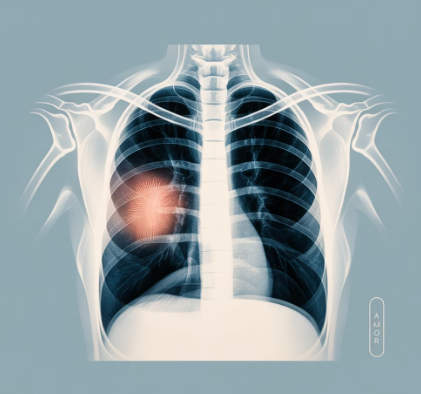

폐암 가능성

만성 기침은 드물지만 폐암의 신호일 수도 있습니다. 기존에 없던 기침이 새로 생기거나, 피 섞인 가래, 체중 감소, 호흡 곤란 등이 동반되면 반드시 검진을 받아야 합니다. 조기 발견이 무엇보다 중요합니다.